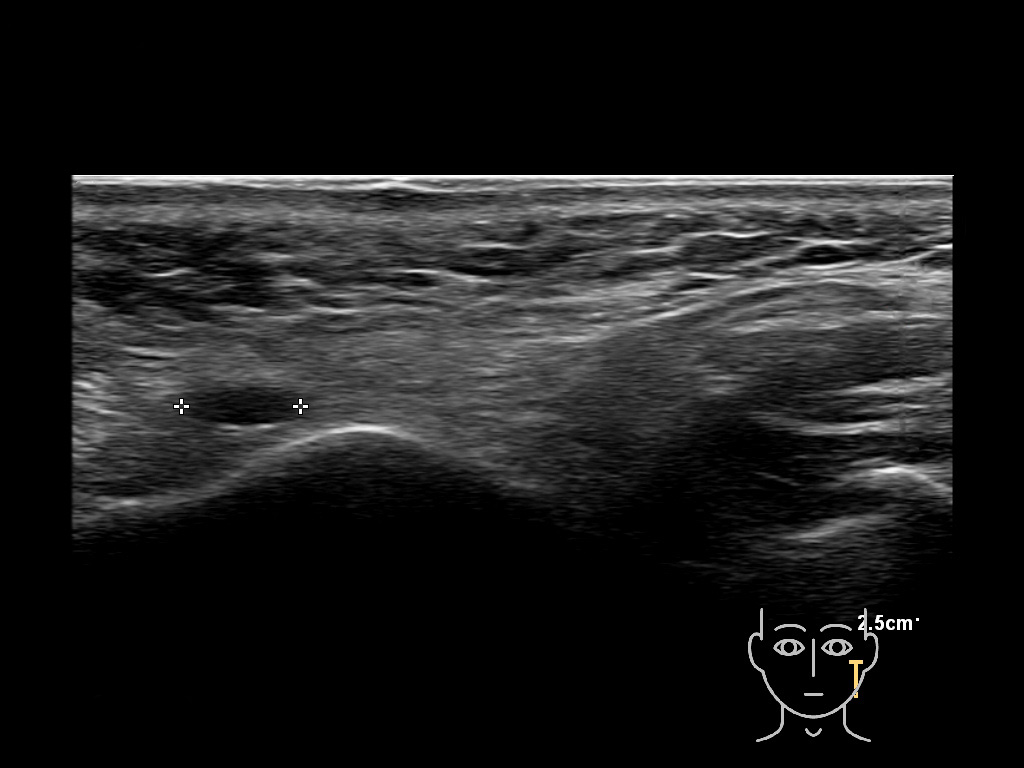

Filler injections in the parotid gland may go unnoticed, however, inflammatory reactions and abscesses may occur. Hypervascularity can be seen with color doppler. Filler deposits are supposed to be injected into the superficial fatty layer . The space to inject into this layer may be limited. Routinely we measure a width of 2-4 millimeters with sometimes subcutaneous layers being less than one millimeter thick.

Study the first image to recognize the different layers. If you are sure about the layers, swipe to the second image to view the answer (if applicable).

Hover over an image to view the secondary image or click on the image title for more information.